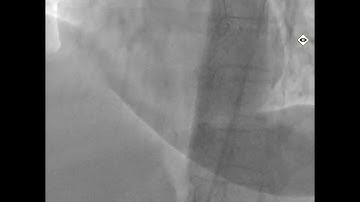

Retrograde approach to RCA CTO